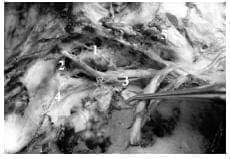

1. Compartimientos postero superior y medial del seno cavernoso derecho:

1-Compartimiento medial

2- compartimiento postero superior

3-VI par

4-Membrana del foramen lacerado anterior

5-N. Óptico; III, IV, V1 replegados con el disector hacia delante.